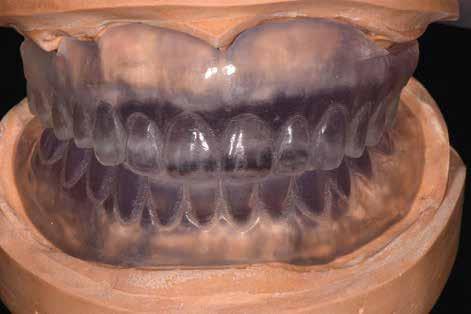

Hagyományos teljes fogsor hatékony átalakítása

A hagyományos teljes kivehető fogpótlási technikákkal a kezelési stratégia a felső és alsó állcsont kapcsolatának és az okkluzális vertikális dimenzió és a fog helyzetének meghatározását foglalta magában, majd az alsó rögzített restauráció előállításához ezeket használták fel referenciákként (3. ábra) 11